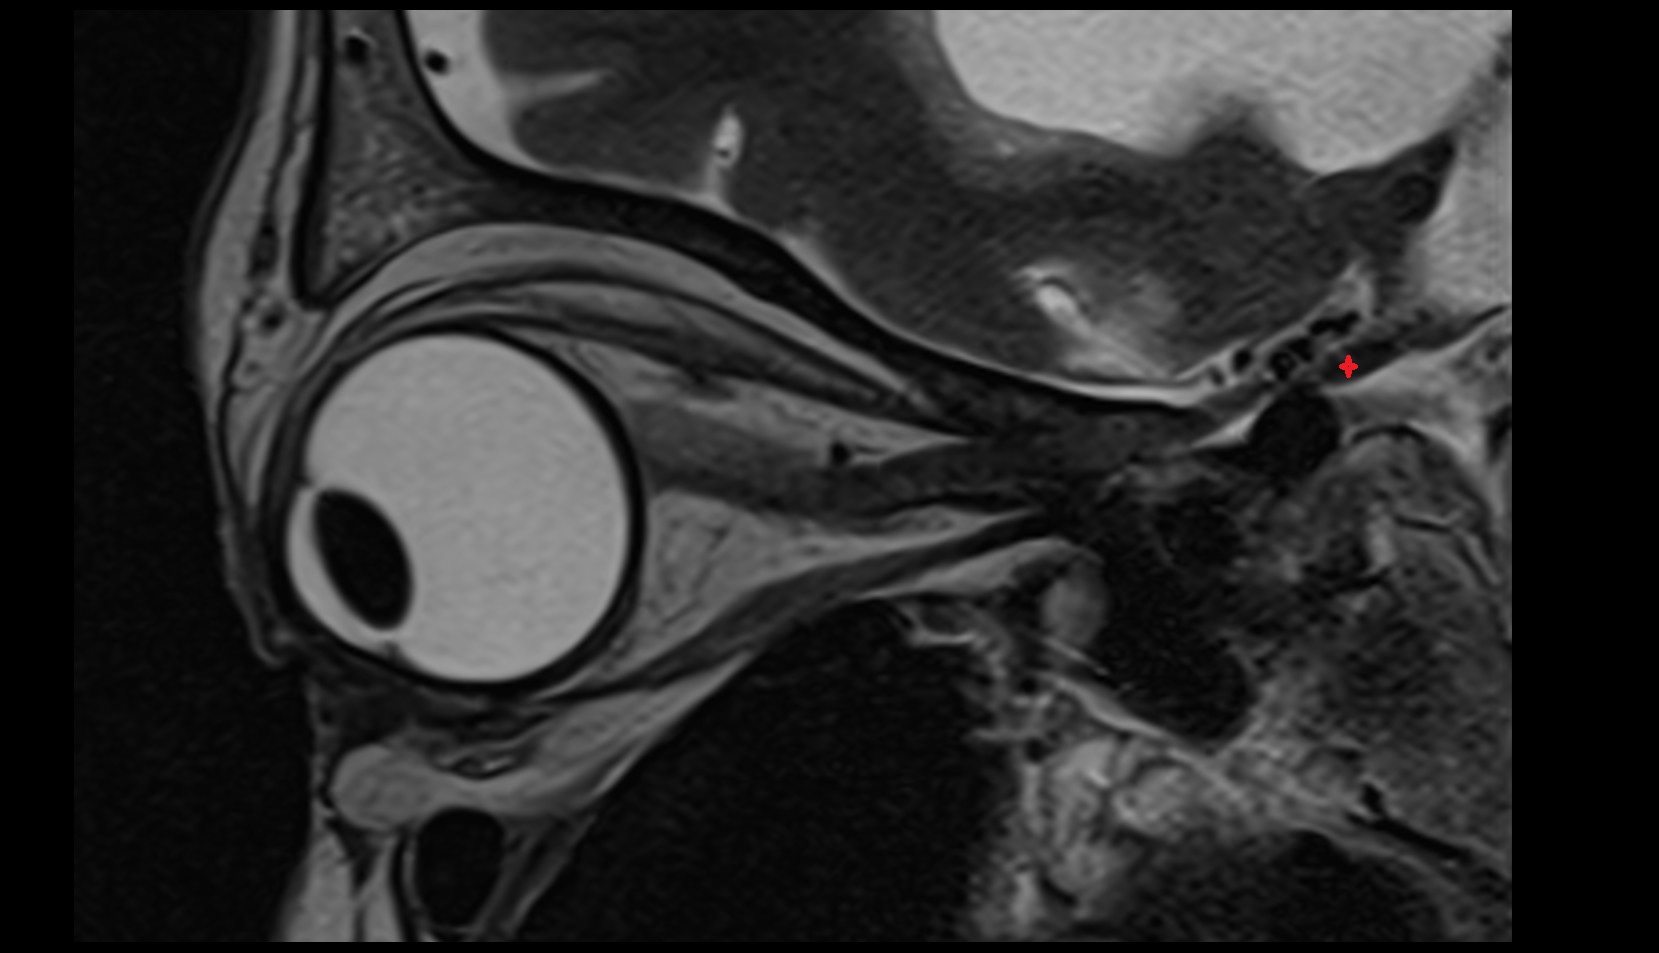

- Uterus

- Body of uterus

- Fundus of uterus

- Cervix of uterus

- Isthmus of uterus

- Vagina

- Fornix of the vagina

- Endometrium of uterus

- Myometrium of uterus

- Perimetrium of uterus

- Junctional zone of uterus